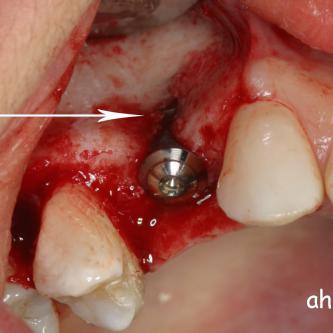

Exemple 11: Pendant l'implantation on remarque un manque d'os sur la partie externe, les spires de l'implant sont visibles.

Exemple 11: Une greffe d'os est effectuée afin de compenser l'épaisseur d'os manquante.